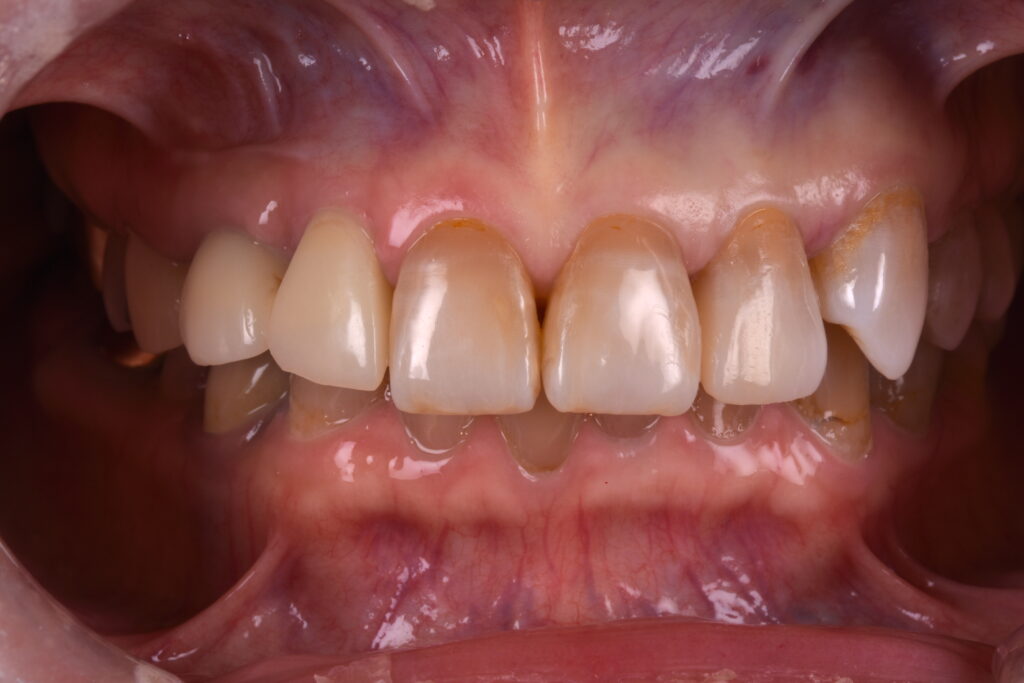

それぞれの治療においてメリットとデメリットがありますが、今回は自身の歯をなるべく削らないことに重点をおいて、③のダイレクトボンディングにより治療を行うこととしました。

周囲の歯の色と馴染ませるために、数種類の色のコンポジットレジンと用いて積層に充填を行い研磨をしました。コンポジットレジン(歯科用樹脂)の歯に対する接着力や物性の向上により、綺麗な状態が長続きするようになってきました。

ご自身の天然の歯を最大限残せることが、このダイレクトボンディングの大きな魅力だと思います😊